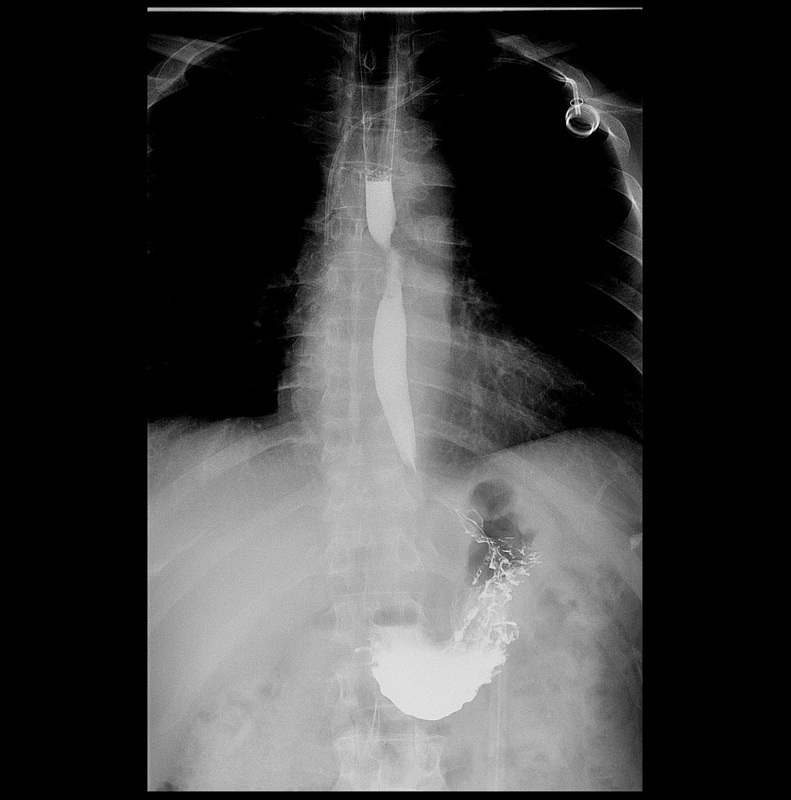

即使是第四期食道癌患者,也不是完全沒有希望。徐中平副院長指出,經過適當的治療,有些患者的病情依然可以獲顯著的改善,甚至可以達到手術治療的條件;曾有左主支氣管受腫瘤侵犯的55歲男性,經放射及化學治療後,病理報告顯示病灶顯著縮小,且無淋巴轉移。他除了建議年過四十的民眾定期健檢之外,一旦有吞嚥卡卡感覺等症狀時,務必就醫檢查,早期診斷、治療,對病人幫助最多,且大大提高成功治療的機率。

圖:圖為55歲食道癌患者,放化療後,上消化道以鋇劑X光攝影,已無黏膜皺襞破壞、管壁僵硬,管腔狹窄,鋇劑通過受阻等病兆。(徐中平提供)